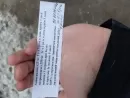

Пришел ставить пломбу, запломбировали каналы, поставили временную пломбу. Через 2 часа десна начала пухнуть. Стоматология уже была закрыта (воскресенье вечер), на утро я снова туда, мне проткнули опухшую десну, открыли один канал из 3-х самый крупный, сказали полоскать содой, и приходить через пару дней. Десна (свищ) в месте прокола назревала к вечеру, с утра лопнула, с выделением гноя. Я больше не мог терпеть, поэтому поехал еще раз на разрез. Разрезали, поставили дренаж, назначили антибиотики, и полоскание Хлоргексидином, и установку временной пломбы. Все вроде хорошо. Показался стоматологу-хирургу через 5 дней, вроде не болит ничего, чтобы перестраховаться оставили дренаж до субботы. Сегодня придя с работы с ночной смены, нажал я на десну и оттуда начал вытекать гной. Решил ехать делать полный снимок зубов, а то дренаж снимут и снова все повторится.